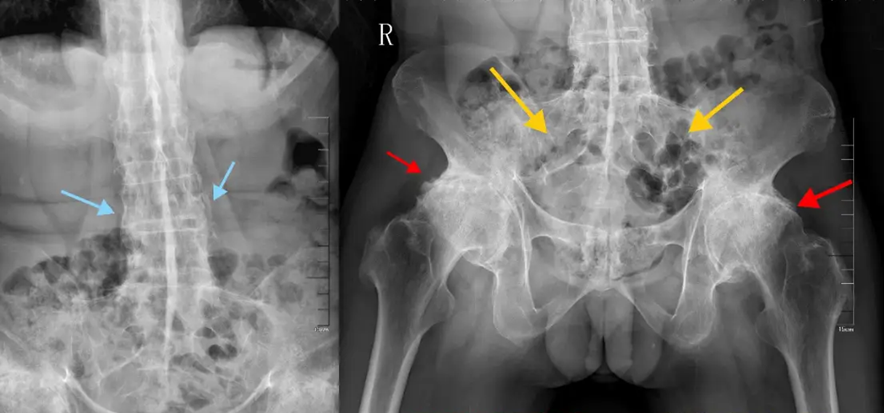

Bệnh tật 20 năm của Châu Kiệt Luân đang tấn công giới trẻ!- Ảnh 2.

Cột sống của bệnh nhân bị viêm cột sống dính khớp có những thay đổi "giống như cây tre"